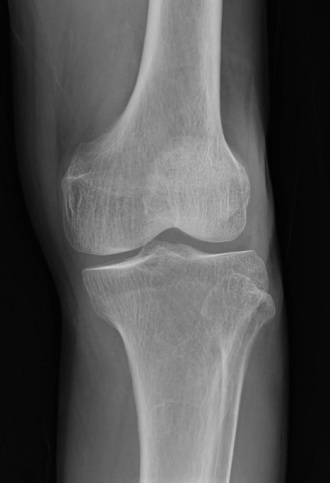

この写真の患者さんは、農道の側溝に落ちて左膝の痛みで受診されました。

レントゲンでは明らかな骨折は認めませんでしたが、痛みが強くMRIを施行して骨折と診断しました。

上段がレントゲン画像で、下段がMRI画像で、黄色く囲ったところが骨折部位です。